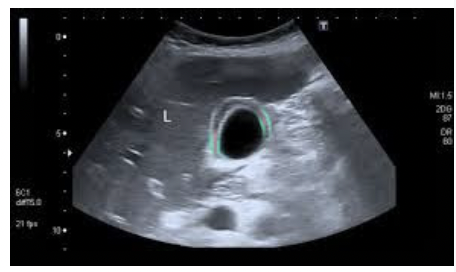

What pathology is in the image below ?

Acute Choleycystitis - Thickened gallbladder wall >3 mm, irregular outline of thickened wall, sonolucent